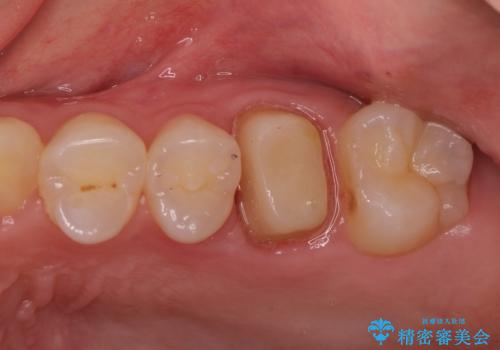

金属の奥歯 → 白い奥歯 根管治療からのやり直し

- 再根管治療→土台の築造 を行った上でのかぶせ物のやり替えをおこないました。

神経の無い歯のかぶせ物をやり替える際は、是非根管治療からしっかりやり直すことをおすすめします。